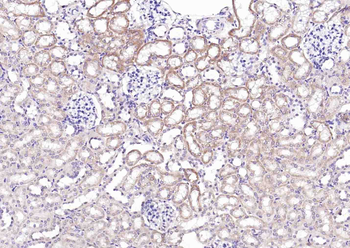

Phospho-TIRAP (Tyr86) Rabbit Polyclonal Antibody抗体

Phospho-TIRAP (Tyr86) Rabbit Polyclonal Antibody

TIRAP

FC, IF, IHC-Fr, IHC-P, WB

KLH conjugated Synthesised phosphopeptide derived from human TIRAP around the acetylation site of Tyr86 KD(p-Y)DV

应用稀释比例:WB=1:500-2000, IHC-P=1:100-500, IHC-F=1:100-500, IF=1:100-500, Flow-Cyt=2ug/Test